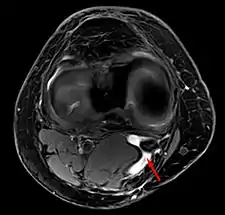

- Baker's cyst on axial MRI with communicating channel between the semimembranosus muscle and the medial head of the gastrocnemius muscle.